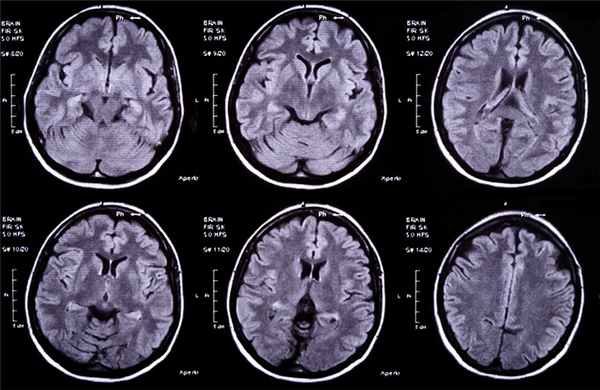

Начальная стадия соответствует ограниченному энцефалиту (церебриту) и обычно характеризуется не резко выраженными изменениями неспецифического характера на фоне обострения хронического гнойного среднего отита – нелокализованной головной болью, недомоганием. Впоследствии происходит ограничение (барьеризация) воспалительного процесса, сопровождаемое минимизацией клинических проявлений заболевания (латентная стадия). Для этого периода характерно отсутствие какой-либо отчетливой симптоматики. Важными клиническими признаками сформированного абсцесса мозга (явная стадия) являются общеинфекционые (слабость, повышение температуры тела, изменения в периферической крови), общемозговые (головная боль, тошнота, рвота, брадикардия, застойные изменения на глазном дне) и очаговые симптомы. Последние зависят от локализации абсцесса. К признакам абсцесса височной доли относят контрлатеральный гемипарез, центральный паралич лицевого нерва, судороги, атаксию, нарушения вкуса и обоняния, гомонимную гемианопсию, алексию, аграфию, а при поражении доминантной доли – сенсорную и амнестическую афазию. К очаговым симптомам абсцесса мозжечка относят координационные расстройства, понижение сухожильных рефлексов на стороне поражения, появление патологических рефлексов и др. При вторичном гнойном менингите у больных с абсцессом мозга наблюдается менингеальный синдром с характерными изменениями спинномозговой жидкости. Вместе с тем многообразие клинических проявлений отогенного абсцесса мозга, его частое сочетание с другими внутричерепными осложнениями затрудняют своевременную диагностику. Именно поэтому одним из наиболее эффективных методов диагностики отогенных абсцессов мозга является КТ [24–26]. При проведении КТ визуализируется участок мозга пониженной плотности с ровными краями и выраженной зоной перифокального отека, усилением визуализации капсулы при введении контрастного вещества [27].

По оценкам экспертов, высокой, сопоставимой с КТ чувствительностью при абсцессах мозга обладает МРТ. При абсцессах мозга на стадии церебрита чувствительность МРТ превышает чувствительность КТ [29].

Для того чтобы провести точную диагностику места расположения абсцесса мозга и мозжечка, проводят компьютерную и магнитно-резонансную томографию головного мозга. При проведении компьютерной томографии выявляется тонкая, гладкая стенка абсцесса, которая имеет правильные контуры. Магнитно-резонансная томография позволяет также определить капсулу абсцесса. Если нет возможности провести вышеперечисленные виды исследования, можно провести пневмоэнцефалографию или радиоизотопную сцинтиграфию головного мозга.